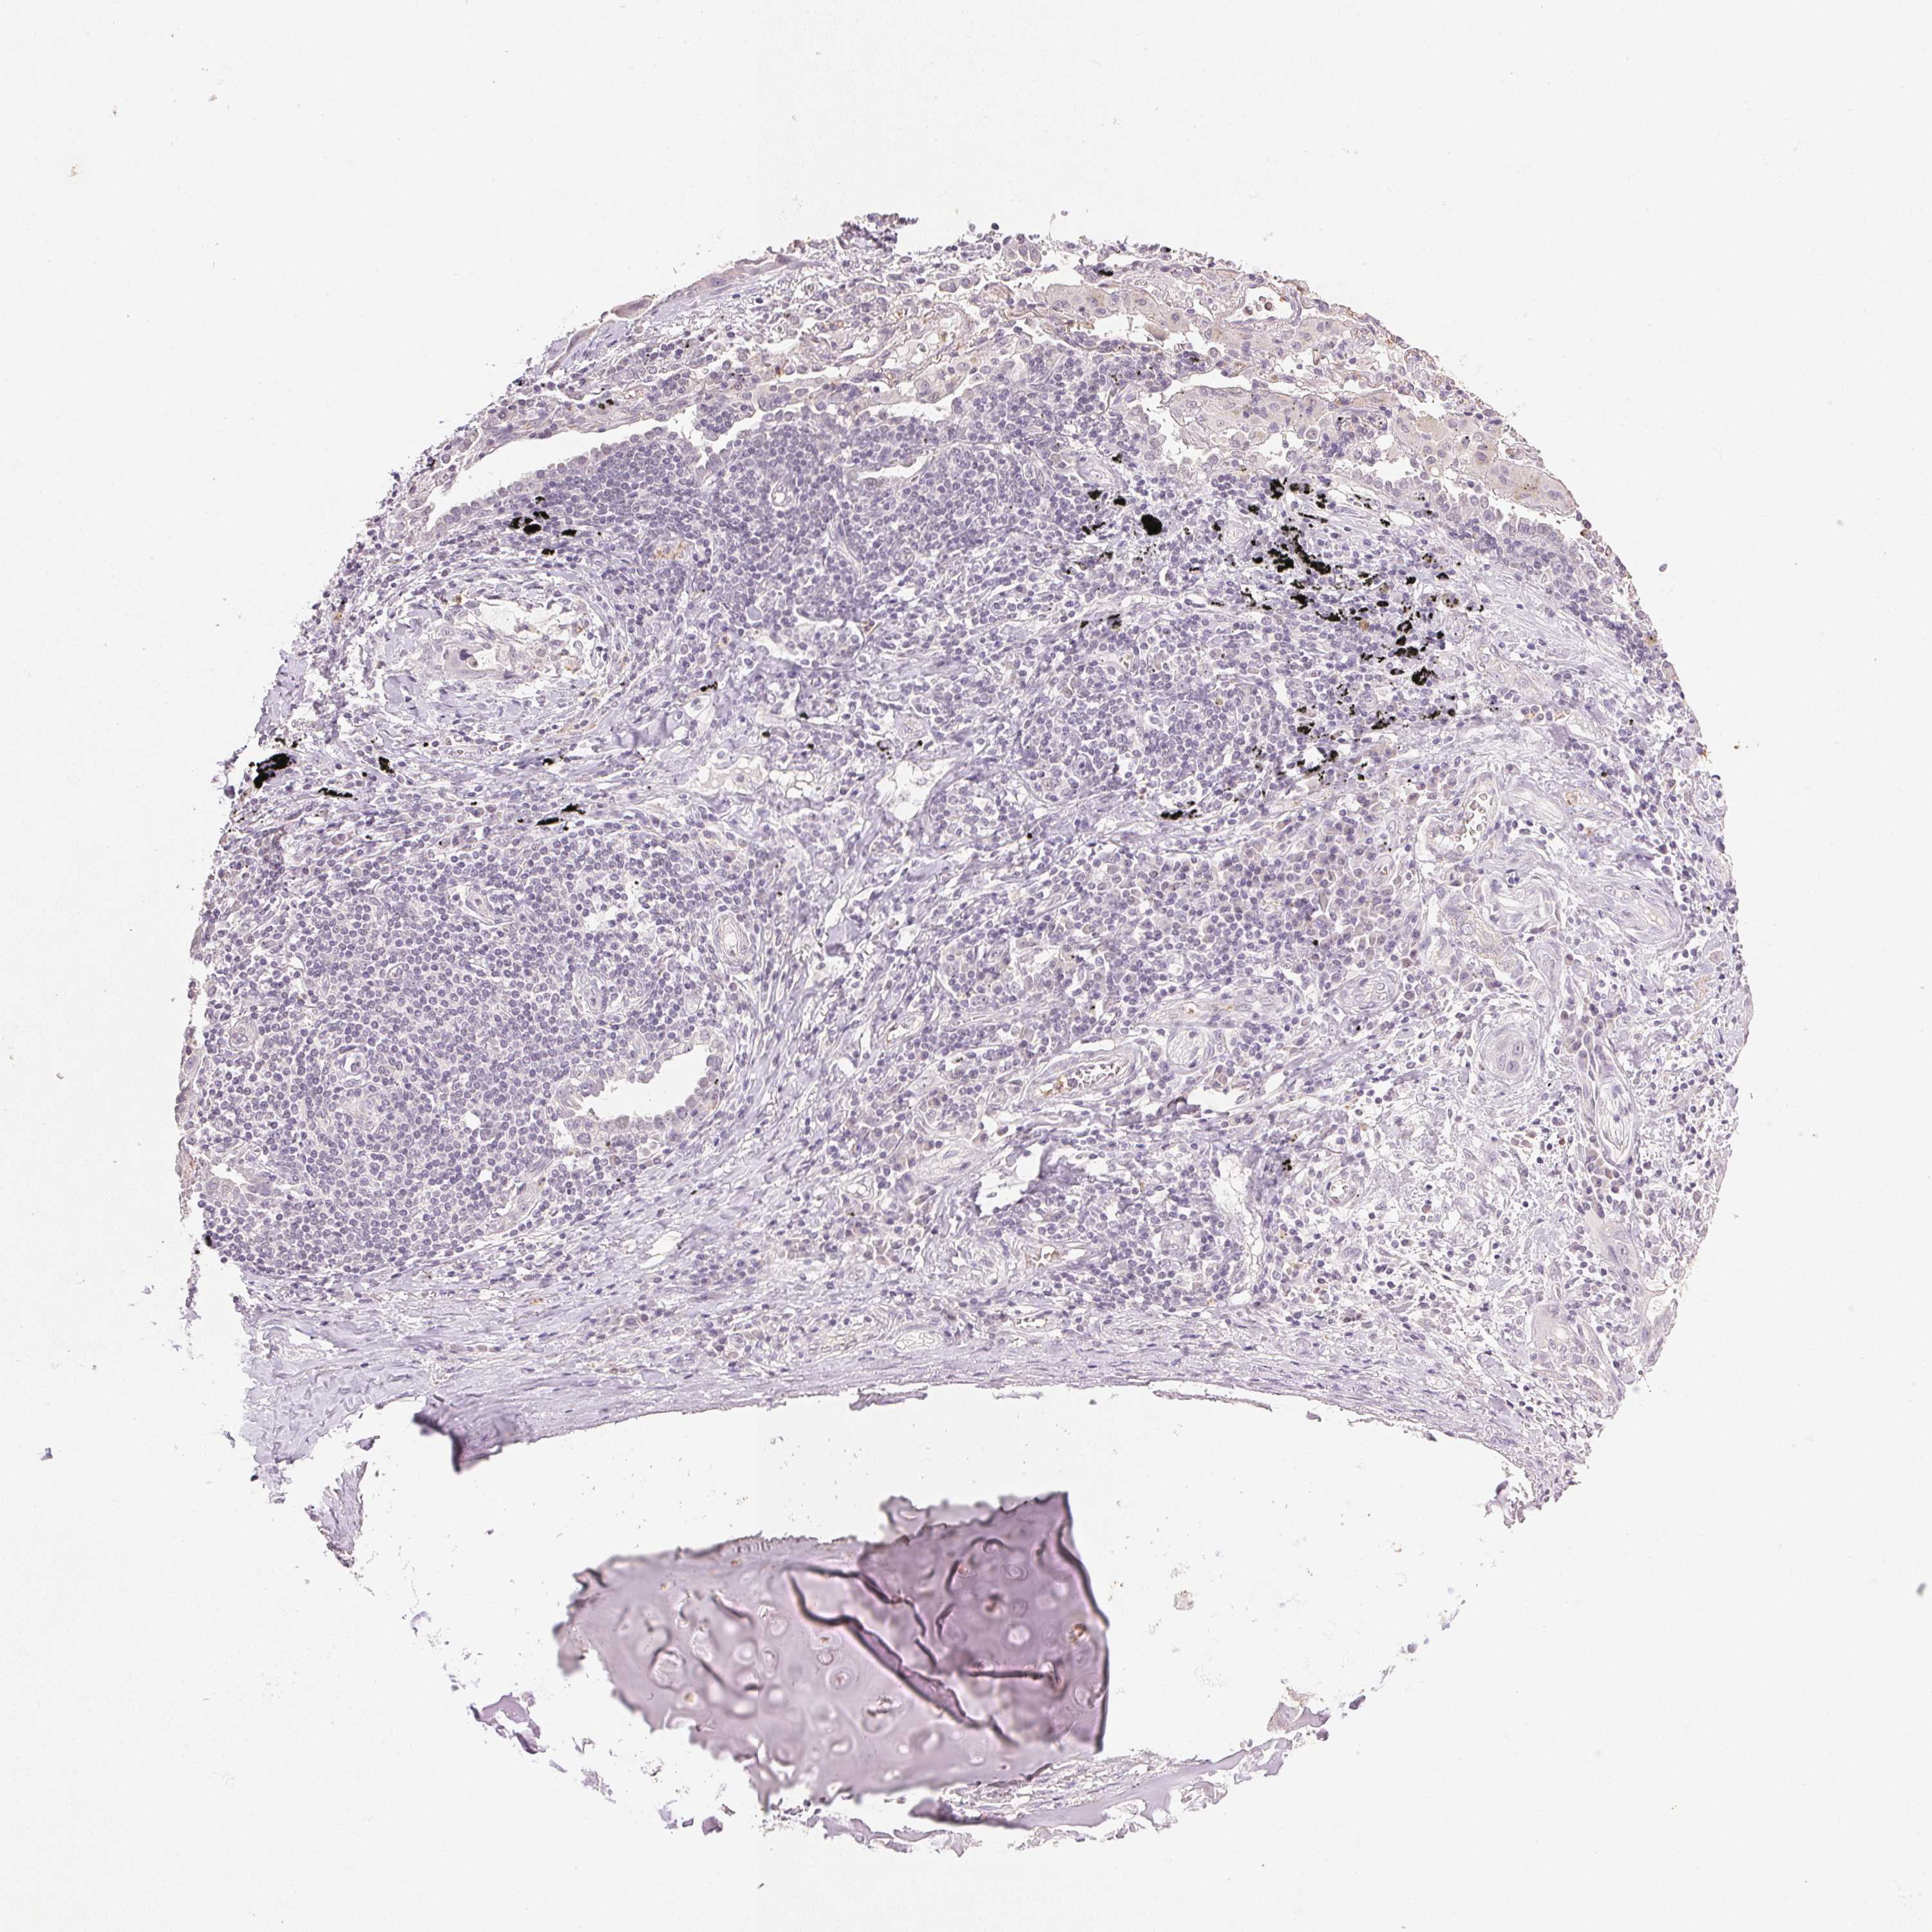

LUNG ADENOCARCINOMA (VALIDATION) - Interactive survival scatter ploti

The Survival Scatter plot shows the clinical status (i.e. dead or alive) for all individuals in the patient cohort, based on the same data that underlies the corresponding Kaplan-Meier plots. Patients that are alive at last time for follow-up are shown in blue and patients who have died during the study are shown in red.

The x-axis shows the expression levels (FPKM) of the investigated gene in the tumor tissue at the time of diagnosis. The y-axis shows the follow-up time after diagnosis (years). Both axes are complimented with kernel density curves demonstrating the data density over the axes. The top density plot shows the expression levels (FPKM) distribution among dead (red) and alive patients (blue). The right density plot shows the data density of the survived years of dead patients with high and low expression levels respectively, stratified using the cutoff indicated by the vertical dashed line through the Survival Scatter plot. This cutoff is automatically defined based on the FPKM cutoff that minimizes the p-score. The cutoff can be changed by dragging the vertical line or by entering a cutoff value in the square labeled "Current cut-off".

Under the Survival Scatter plot the p-score landscape (black curve; left axis) is shown together with dead median separation (red curve; right axis). Dead median separation is the difference in median mRNA expression between patients who have died with high and low expression, respectively. It is calculated as follows: median FPKM expression of dead patients with high expression - median FPKM expression of dead patients with low expression. This is intended to aid the user in visually exploring custom cutoffs and the associated p-scores and dead median separation.

Individual patient data is displayed and can be filtered by clicking on one or more of the category buttons on the top of the page. Categories describing expression level and patient information include: high, low, alive, dead, female, male and tumor stages. The scale of the x-axis can be toggled between linear and log-scale by clicking on the "x log" button. Mouse-over function shows TCGA ID, patient information and mRNA expression (FPKM) for each patient.

& Survival analysisi

Kaplan-Meier plots summarize results from analysis of correlation between mRNA expression level and patient survival. Patients were divided based on level of expression into one of the two groups "low" (under cut off) or "high" (over cut off). X-axis shows time for survival (years) and y-axis shows the probability of survival, where 1.0 corresponds to 100 percent.

SMTN is not prognostic in Lung Adenocarcinoma (validation)

: 10.73